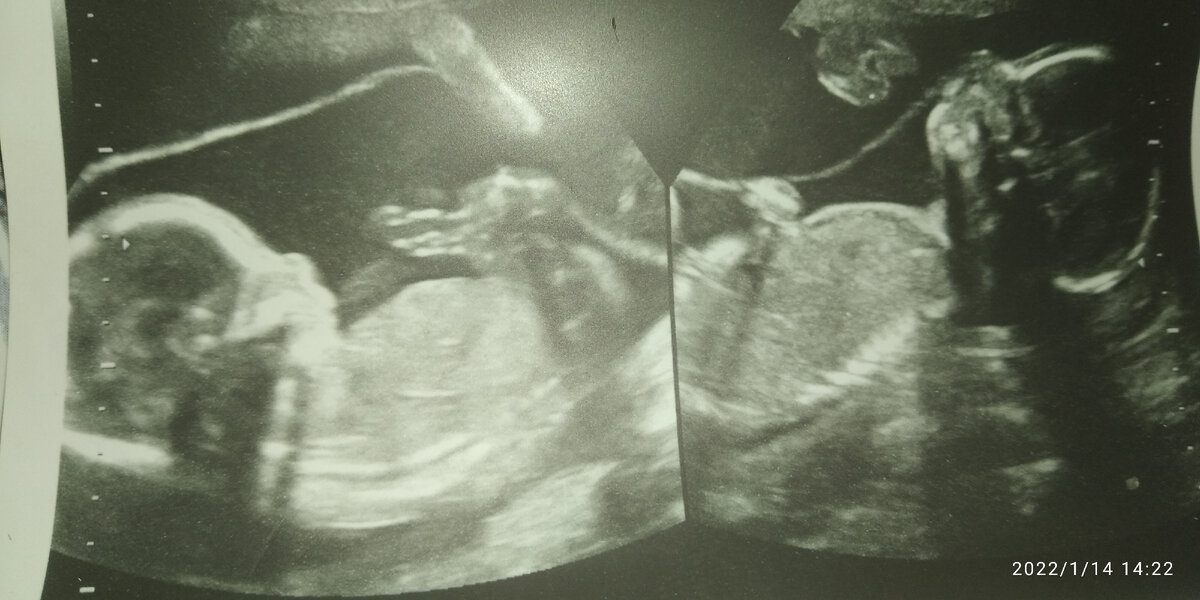

Тут мальчишкам 20 недель.